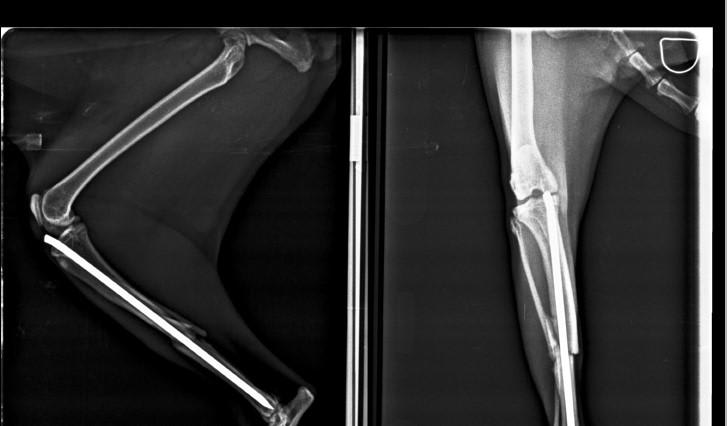

My cat broke her right back leg month ago, was operated & plate was inserted. 10 days later her leg twisting to the right. I took her back to the vet, he said she needs a new surgery. Surgery done yesterday. Back home the same day because the vet said she is fierce & better she stays in a familiar environment. She's on antibiotic (Amoicillin/clavulanicc acid 457mg/5ml) dose is 1ml twice a day. she isn't eating well, but taking medication. Just to know if surgery went good and about recovery tx

Hello, thank you for using Petco Pet Education Center, formerly Petcoach. From what I can tell from the x-rays the surgery looks successful. It appears they started with an intramedullary pin and then went to using a plate which is more stable. The antibiotic she is on can cause some inappetence so I suggest you try feeding her some other foods to entice her like canned tuna, boiled chicken, etc. and ALWAYS give the antibiotic after she has eaten at least a few bites of food. If her appetite does not improve then speak to the vet about maybe switching antibiotics. I am not exactly sure what else you want to know. If you have more questions please post again and be as specific as possible. I am not sure what you mean by "recovery tx". Hope this helps. Best wishes.